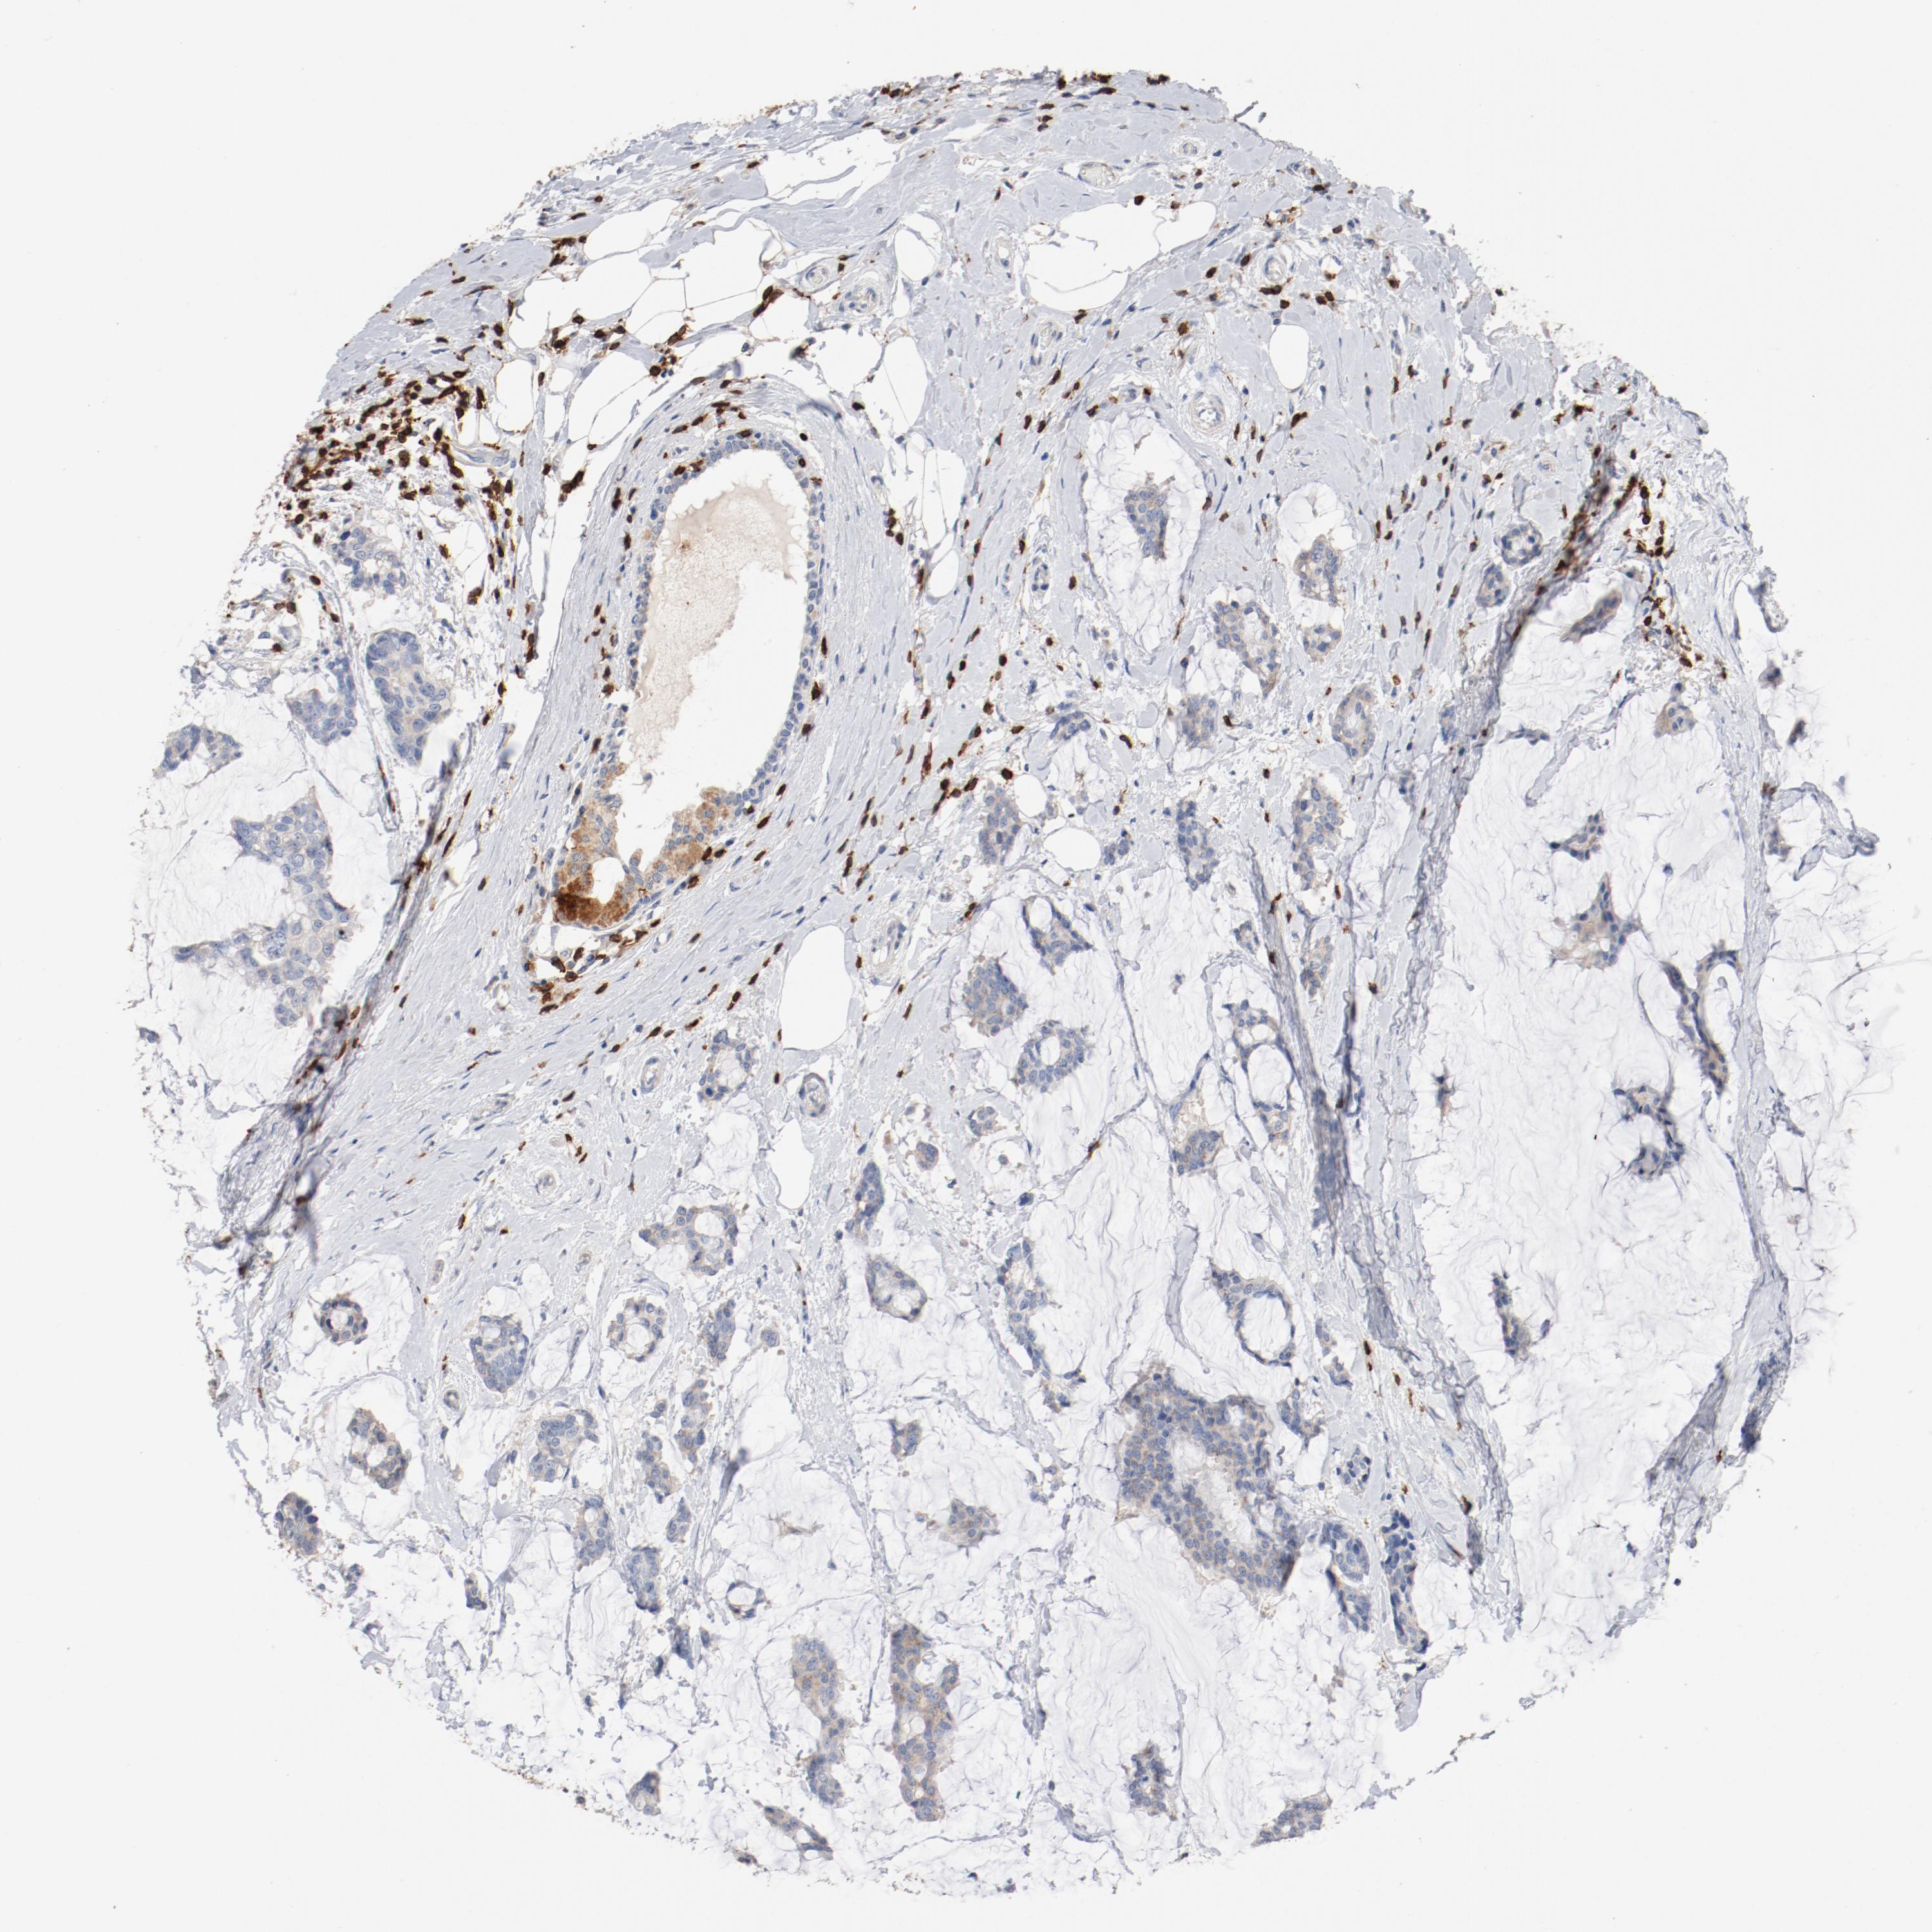

BRCA TCGA BRCA VALIDATION PROTEIN EXPRESSION

ANTIBODIES

AND

VALIDATION